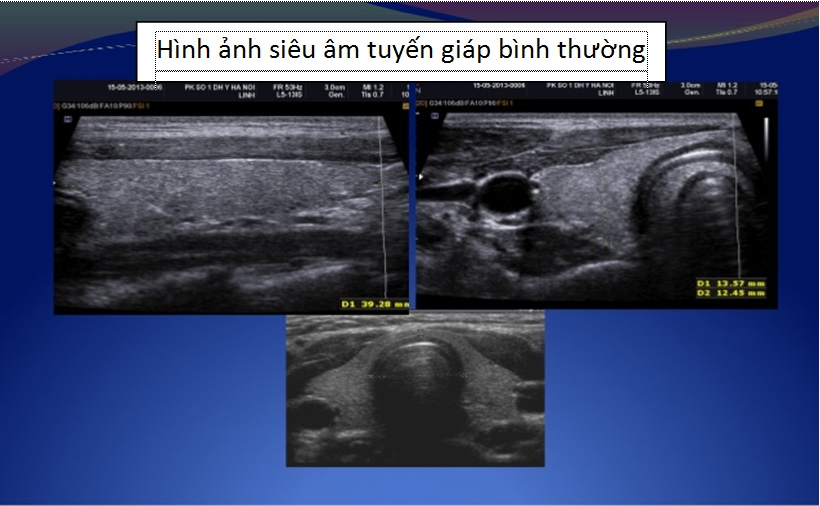

Siêu âm tuyến giáp:

Xác định các bệnh của tuyến giáp: nang, nhân đặc, bướu giáp, cường giáp,…

Hình 5. Siêu âm tuyến giáp